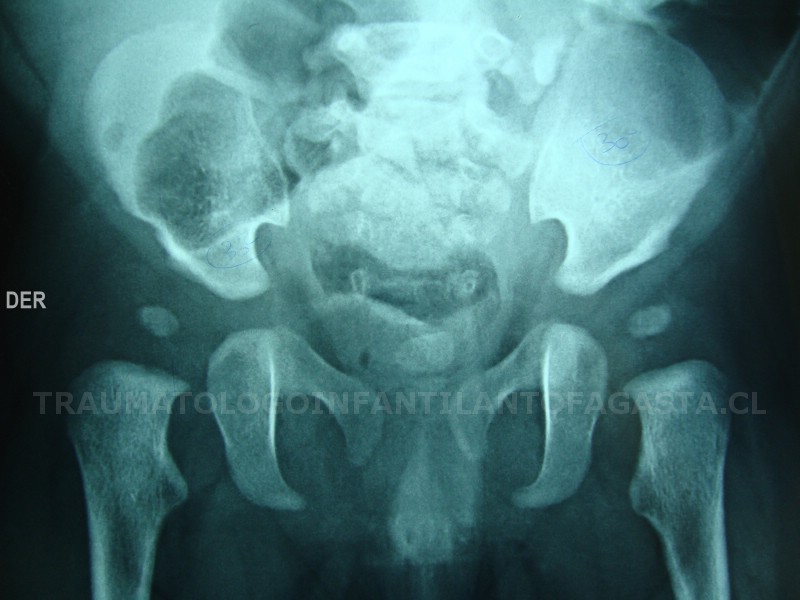

Epifisiolisis de cadera